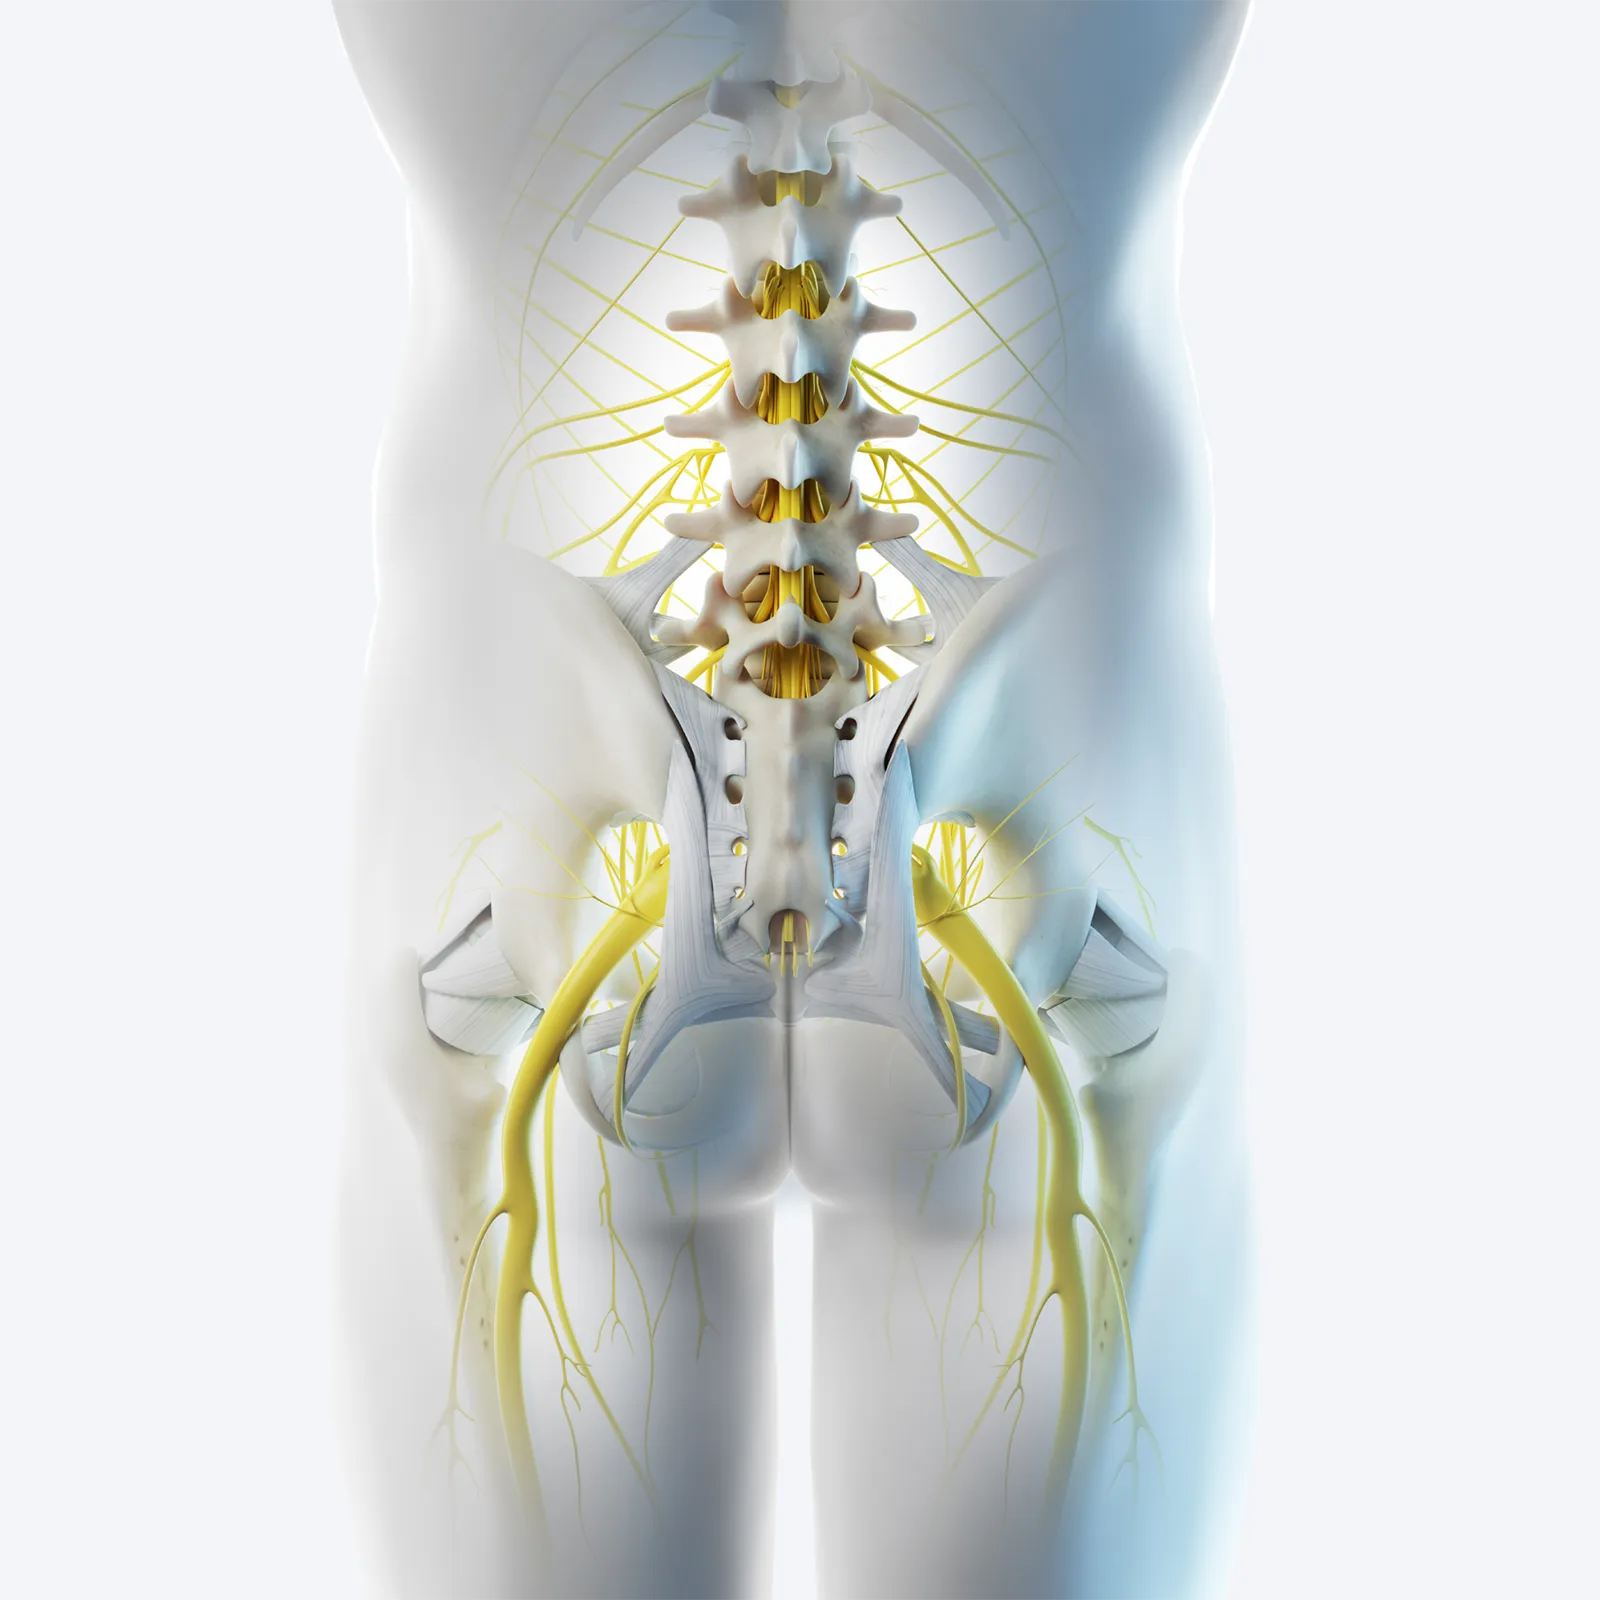

DGS is an umbrella term for several conditions where the sciatic nerve or other peripheral nerves passing through the gluteal region become compressed or irritated by muscles, connective tissues, or vascular structures (Image 1).

Unlike lumbar radiculopathy (where nerve irritation originates in the spine), DGS involves entrapment at the level of the hip and pelvis, most often beneath or between the muscles of the deep six lateral rotators. While sciatic nerve entrapments are the most common, the definition extends to entrapments of the pudendal, superior and inferior gluteal nerves, obturator, and posterior femoral cutaneous nerves. Massage therapists are most familiar with the following syndromes: